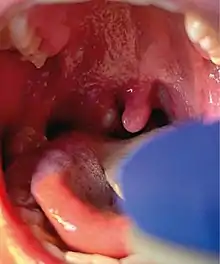

Mpox is a viral infection that manifests a week or two after exposure with fever and other non-specific symptoms, and then produces a rash with lesions that usually last for 2–4 weeks before drying up, crusting and falling off.[10] While mpox can cause large numbers of lesions, in the current outbreak, some patients experience only a single lesion in the mouth or on the genitals, making it more difficult to differentiate from other infections.[19] In infections before the current outbreak, 1–3 per cent of people with known infections have died (without treatment). Cases in children and immunocompromised people are more likely to be severe.[20]

In addition to more common symptoms, such as fever, headache, swollen lymph nodes, and rashes or lesions, some patients have also experienced proctitis, an inflammation of the rectum lining. CDC has also warned clinicians to not rule out mpox in patients with sexually transmitted infections since there have been reports of co-infections with syphilis, gonorrhea, chlamydia, and herpes.[96]